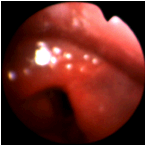

A closer view of the larynx of the patient with reflux, in the previous image. (Selner slide #49) |

![]() |